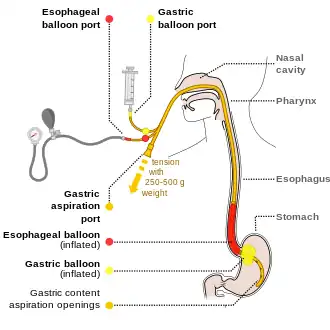

For initial fluid replacement colloids or albumin is preferred in people with cirrhosis.[19] Medications typically includes octreotide or if not available vasopressin and nitroglycerin to reduce portal pressures.[25] This is typically in addition to endoscopic banding or sclerotherapy for the varices.[25] If this is sufficient then beta blockers and nitrates may be used for the prevention of re-bleeding.[25] If bleeding continues then esophageal balloon tamponade with a Sengstaken-Blakemore tube or Minnesota tube may be used in an attempt to mechanically compress the varices.[25] This may then be followed by a transjugular intrahepatic portosystemic shunt.[25]